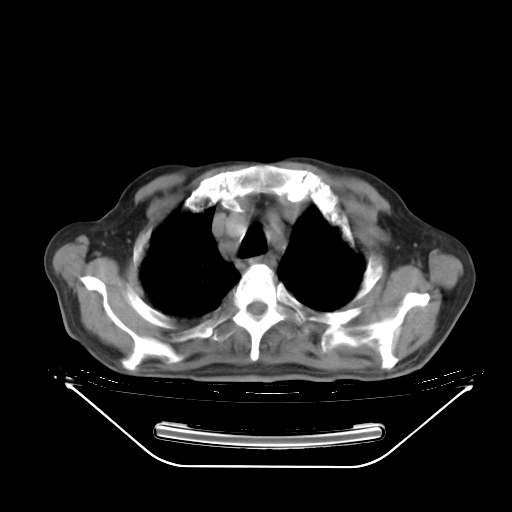

胸腹部CT,诊断意见:左上肺叶钙化灶、左侧胸膜局限性增厚并钙化、胆囊炎。描述部分肺组织呈磨玻璃样改变。

今天复查肺部CT,发现双肺广泛磨玻璃样改变。所以我把3月19日和5月9日相隔50天的肺部CT上传。请大家会诊。

2009年3月19日肺部CT片。

2009年3月19日肺部CT